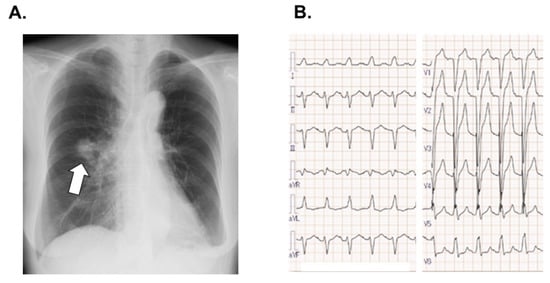

2.2. On Admission

2.3. In-Hospital Course